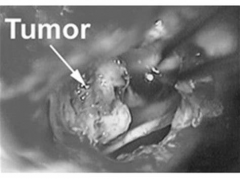

• 听神经瘤手术风险大吗?巨型听神经瘤7次复发并压迫脑干,如何挽救危重患者?

听神经瘤手术风险大吗?巨型听神经瘤7次复发并压迫脑干,如何挽救危重患者?

【听神经瘤案例】听神经瘤手术风险大吗?听神经瘤反复手术、复发并恶化,手术治疗分析,十几年前,我因为发作性右耳闷痛和舌头麻痹去医院检查,...